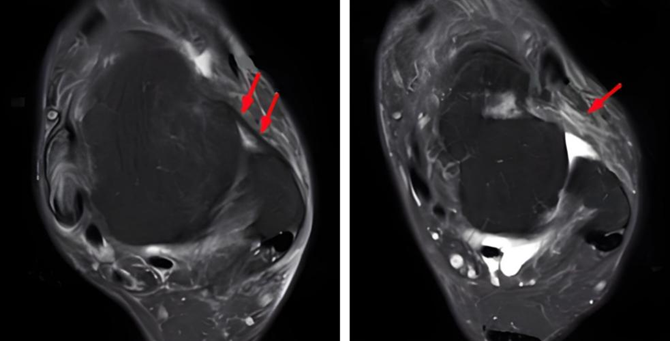

▶核磁共振显示距腓前韧带异常。

图10:左图为正常距腓前韧带(箭头所示),右图为距腓前韧带断裂(箭头所示)

(十)术前核磁共振评估距腓前韧带的损伤程度

▶磁共振下韧带的损伤分型

正常韧带的宽度(1.0-3.2mm);

增厚(>3.2mm);

缺损(<1.0mm)。

图19:左图为正常距腓前韧带(箭头所示),右图为距腓前韧带增厚(箭头所示)